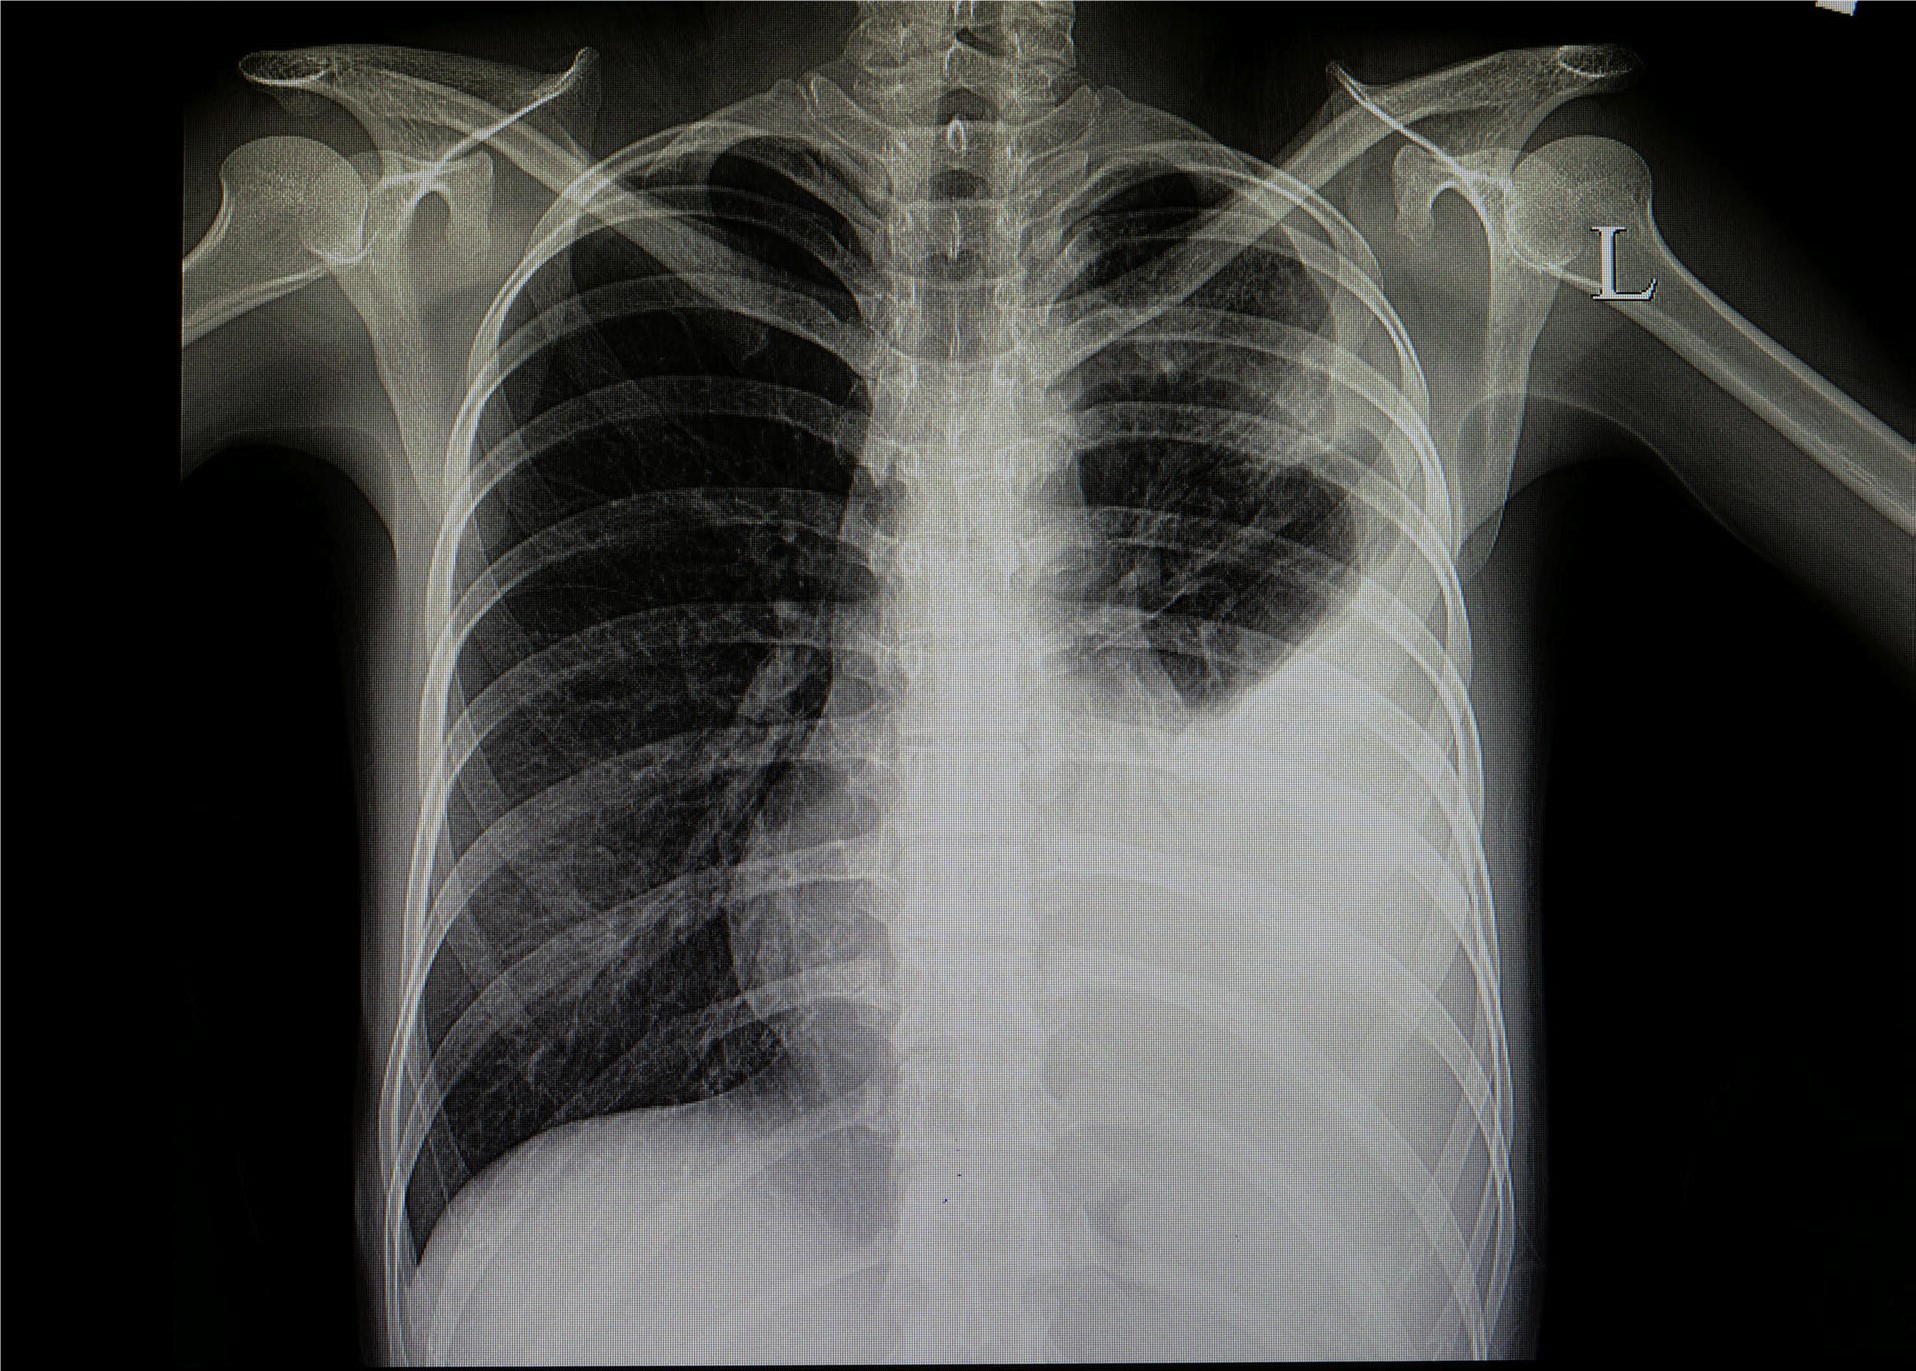

Prof. Dr. Alexander Jesser betreute gemeinsam mit seinem Mitarbeiter Roman Radtke die Studentin bei ihrer vielversprechenden Forschungsarbeit. Prof. Jesser erläutert: „Bei einer Erkrankung der Lunge ist das betroffene Gewebe meist weniger transparent für die Röntgenstrahlung und kann durch seine Form und Abgrenzung Aufschluss geben, um welche Art der Krankheit es sich handelt. Eine Covid-19-Erkrankung zeigt meist milchglasartige Veränderungen in beiden Lungenflügeln. Ist eine Erkrankung der Lunge durch eine Infektion mit Bakterien erfolgt, ist mehrheitlich nur ein Flügel der Lunge verändert. Eine gleichmäßige Ausbreitung über alle Bereiche der Lunge ist dabei also ein Hinweis auf eine Covid-19 Infektion.“

Zur automatisierten Auswertung werden die Aufnahmen in einen Standard-PC eingelesen und mit einer speziellen mathematischen Operation der Kontrast erhöht – ein Vorteil bei qualitativ schlechten Aufnahmen, die mit älteren Röntgenanlagen entstehen. Die Software erstellt neben einem Falschfarbenbild, das die Auswertung vereinfachen kann, ein Binärbild, auf welchem sich bereits die Umrisse der Lunge sowie Spuren von geschädigtem Gewebe erkennen lassen. Durch einen weiteren Algorithmus werden die im Binärbild vorhandenen Kanten und Grenzen der einzelnen Bereiche ermittelt. Die Software kann durch weitere Berechnungen Flächen- und Symmetriebetrachtungen vollziehen und anhand dieser mit großer Wahrscheinlichkeit zwischen bakterieller- oder viraler Lungenentzündungen unterscheiden.

Milchglasartige Veränderungen deuten auf eine Covid-19-Infektion hin. Foto: HHN